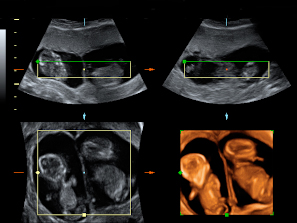

El movimiento de gemelos en el útero encierra sorpresas, como en esta ecografía 4D en la que vemos a dos hermanos en sus respectivas bolsas. El gemelo de la derecha parece estar bailando el "hula hoop" con su propio cordón umbilical, que le rodea las piernas formando un círculo. Destaca la posición casi erguida del niño dentro del útero materno, casi a punto de dar un paso. Cuando uno de los fetos genera mucho movimiento, suele arrastrar a su gemelo a que se mueva también, aunque esté adormecido.

Ecografía 4D de gemelos de 12 semanas moviéndose: el baile del "hula hoop"